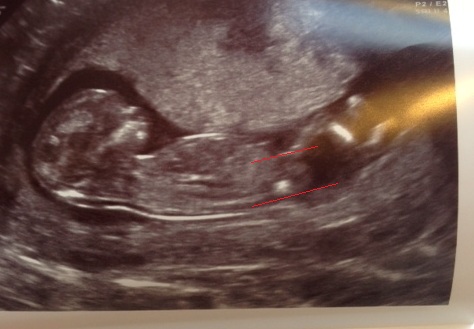

Have attached a picture with the lines drawn in, if it helps anyone, top line goes through the nub.

Attachment 18088

I think boy as the nub looks stacked but I agree it's unclear. Super cute babe!

I'd lean boy, but it's hard to tell. It looks like the nub goes up a bit? Such a cute baby though, congrats with your pregnancy!